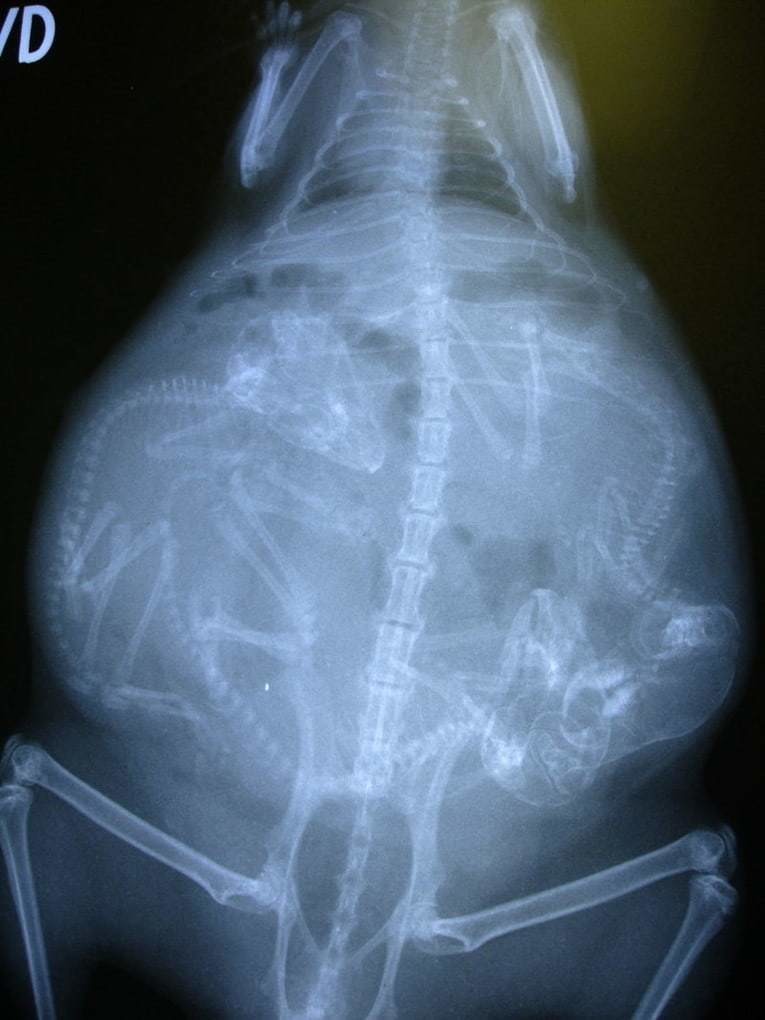

Рентген кошки с котятами в животике